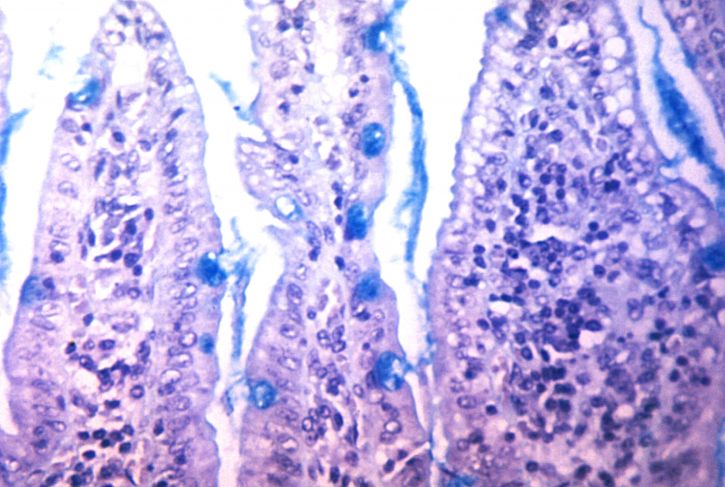

Vibrio Cholerae

2. Conduct a randomized controlled trial of 600 household members of cholera patients to evaluate the effectiveness of the intervention in reducing cholera infections and the presence of the bacteria that causes it, Vibrio cholerae, in the household.

3. Investigate transmission and population dynamics of Vibrio cholerae among households with a cholera patient using whole genome sequencing and spatial mapping.